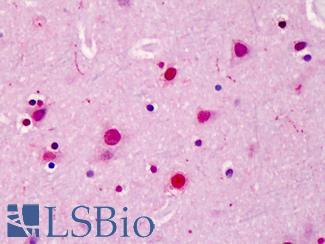

SATB2

Anti-SATB2 antibody IHC of human brain, cortex. Immunohistochemistry of formalin-fixed, paraffin-embedded tissue after heat-induced antigen retrieval. Antibody LS-B4981 concentration 5 ug/ml.